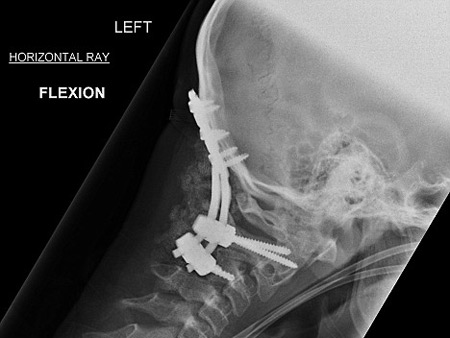

وعقب حصول الحادث في أواخر العام 2006، قام الأطباء بإخضاع الصبي المصاب إلى عملية جراحية عاجلة استمرت لمدة 7 ساعات، وهي العملية التي نجحوا خلالها في إعادة تثبيت فقرات رقبته وتوصيلها إلى قاعدة الجمجمة باستخدام مسامير وشرائح مصنوعة من معدن التيتانيوم.

وقال الأطباء أن أفضل ما كانوا يتوقعونه هو أن يبقى الصبي على قيد الحياة، لكن حالته شهدت تحسنا ملموسا واستمر في التعافي من إصابته بشكل مذهل إلى أن عاد أخيرا إلى مزاولة رياضة سباقات السيارات.